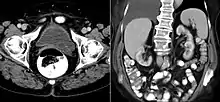

A ureterocele is a congenital abnormality found in the ureter. In this condition the distal ureter balloons at its opening into the bladder, forming a sac-like pouch. It is most often associated with a duplicated collection system, where two ureters drain their respective kidney instead of one. Simple ureterocele, where the condition involves only a single ureter, represents only twenty percent of cases.

Since the advent of the ultrasound, most ureteroceles are diagnosed prenatally. The pediatric and adult conditions are often found incidentally, i.e. through diagnostic imaging performed for unrelated reasons.

- Cobra head sign is seen in radiography

IVU-shows Adder head appearance or Cobra head appearance. Cystoscopy-shows translucent cyst which is thin walled surrounding ureteric orifice